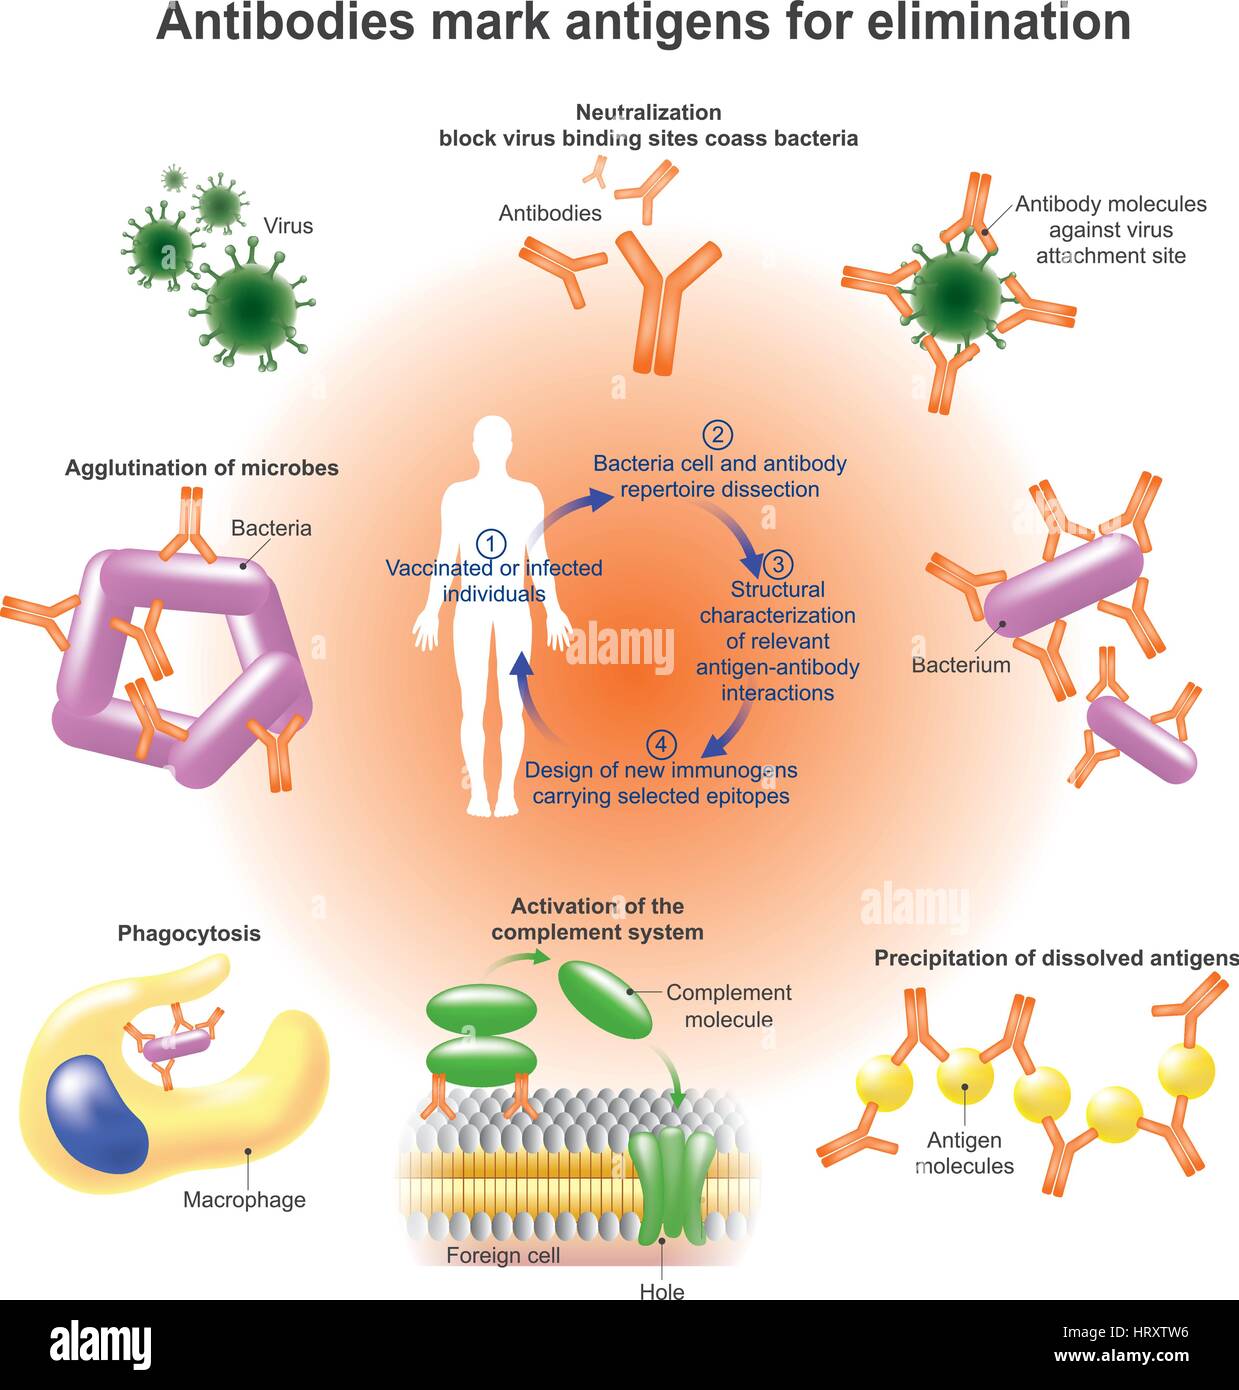

Un anticorpo (Ab), noto anche come una immunoglobulina è una grande a forma di Y proteina prodotta principalmente da cellule di plasma che viene utilizzata dal sistema immunitario Illustrazione Vettorialehttps://www.alamy.it/image-license-details/?v=1https://www.alamy.it/foto-immagine-un-anticorpo-ab-noto-anche-come-una-immunoglobulina-e-una-grande-a-forma-di-y-proteina-prodotta-principalmente-da-cellule-di-plasma-che-viene-utilizzata-dal-sistema-immunitario-135199938.html

Un anticorpo (Ab), noto anche come una immunoglobulina è una grande a forma di Y proteina prodotta principalmente da cellule di plasma che viene utilizzata dal sistema immunitario Illustrazione Vettorialehttps://www.alamy.it/image-license-details/?v=1https://www.alamy.it/foto-immagine-un-anticorpo-ab-noto-anche-come-una-immunoglobulina-e-una-grande-a-forma-di-y-proteina-prodotta-principalmente-da-cellule-di-plasma-che-viene-utilizzata-dal-sistema-immunitario-135199938.htmlRFHRXTW6–Un anticorpo (Ab), noto anche come una immunoglobulina è una grande a forma di Y proteina prodotta principalmente da cellule di plasma che viene utilizzata dal sistema immunitario